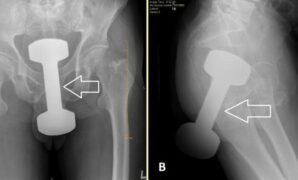

Kisah Dokter Keluarkan Dumbell 2,2 Kg yang Nyangkut di Anus Pria